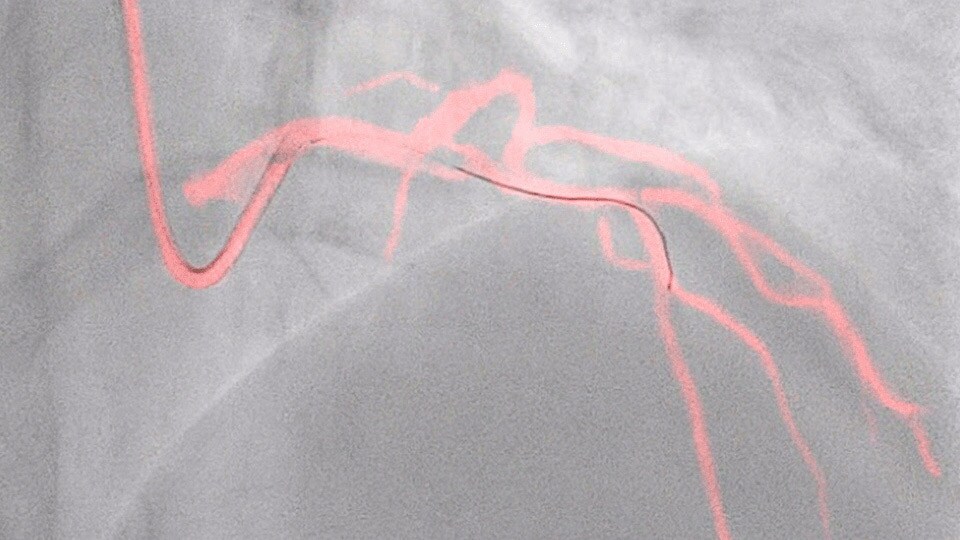

This Philips-exclusive technology provides a real-time view of the coronary arteries and removes the need for additional contrast injections.